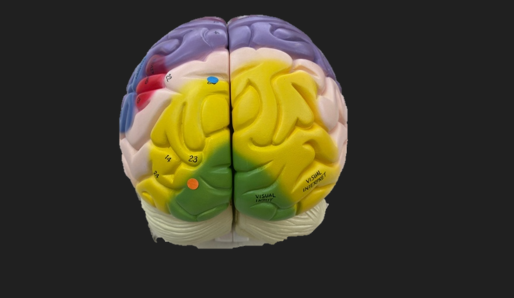

orange dot

frontal lobe

blue dot

longitudinal fissure

dark green dot

precentral gyrus

pink dot

postcentral gyrus

yellow dot

central sulcus

white dot

parietal lobe

light green dot

Broca’s Area

red dot

Wernicke’s Area

orange dot

occipital lobe

blue dot

parieto-occipital sulcus